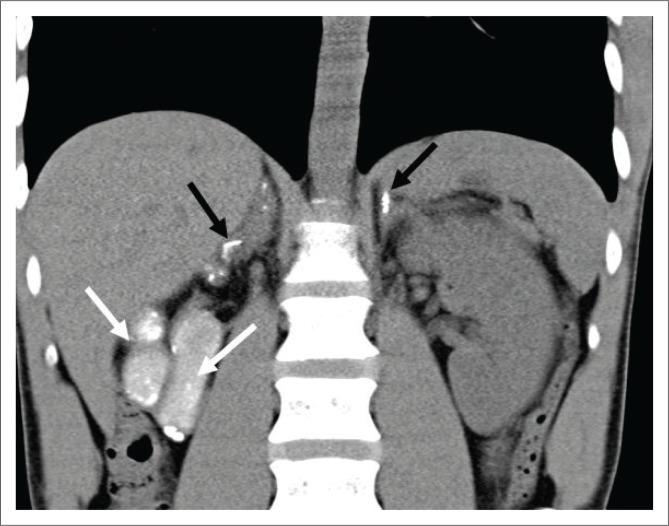

Extra-pulmonary tuberculosis (EPTB), caused by , is the leading cause of communicable disease-related deaths in people with human immunodeficiency virus (HIV) worldwide and in South Africa. disseminates haematogenously from an active primary lung focus and may affect extra-pulmonary sites in up to 15% of patients. Extra-pulmonary TB may present with a normal chest radiograph, which often causes a significant diagnostic dilemma. This review describes the main sites of involvement in EPTB, which is illustrated by local imaging examples.

由……引起的肺外结核病(EPTB)是全球和南非人类免疫缺陷病毒(HIV)感染者中与传染病相关死亡的主要原因。……从活跃的原发性肺部病灶经血行播散,高达15%的患者可能累及肺外部位。肺外结核病可能胸部X线片表现正常,这常常造成重大的诊断困境。本综述描述了肺外结核病的主要受累部位,并通过局部影像学实例进行说明。 (注:原文中“caused by ”和“disseminates haematogenously from an active primary lung focus and may affect extra-pulmonary sites in up to 15% of patients.”前缺失关键信息)